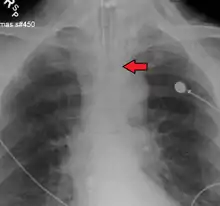

An endotracheal tube not deep enough. Arrow marks the tip.

No single method for confirming tracheal tube placement has been shown to be 100% reliable. Accordingly, the use of multiple methods for confirmation of correct tube placement is now widely considered to be the standard of care.[35] Such methods include direct visualization as the tip of the tube passes through the glottis, or indirect visualization of the tracheal tube within the trachea using a device such as a bronchoscope. With a properly positioned tracheal tube, equal bilateral breath sounds will be heard upon listening to the chest with a stethoscope, and no sound upon listening to the area over the stomach. Equal bilateral rise and fall of the chest wall will be evident with ventilatory excursions. A small amount of water vapor will also be evident within the lumen of the tube with each exhalation and there will be no gastric contents in the tracheal tube at any time.[34]

Ideally, at least one of the methods utilized for confirming tracheal tube placement will be a measuring instrument. Waveform capnography has emerged as the gold standard for the confirmation of tube placement within the trachea. Other methods relying on instruments include the use of a colorimetric end-tidal carbon dioxide detector, a self-inflating esophageal bulb, or an esophageal detection device.[36] The distal tip of a properly positioned tracheal tube will be located in the mid-trachea, roughly 2 cm (1 in) above the bifurcation of the carina; this can be confirmed by chest x-ray. If it is inserted too far into the trachea (beyond the carina), the tip of the tracheal tube is likely to be within the right main bronchus—a situation often referred to as a "right mainstem intubation". In this situation, the left lung may be unable to participate in ventilation, which can lead to decreased oxygen content due to ventilation/perfusion mismatch.[37]